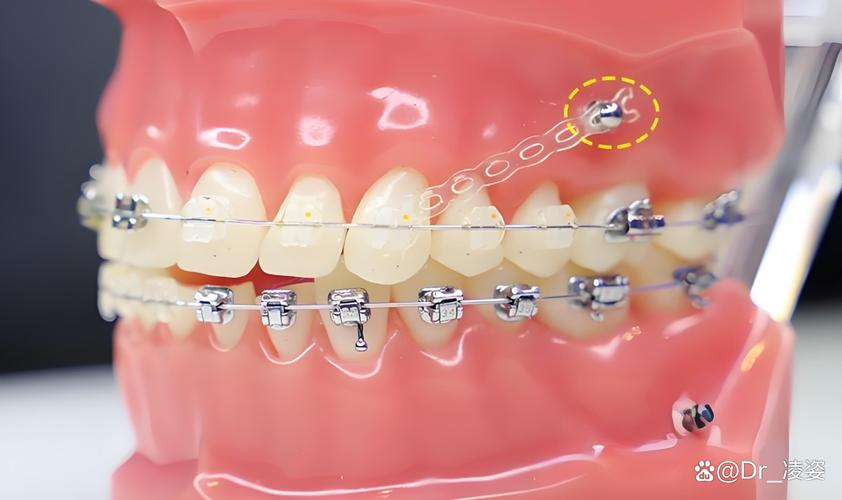

部分患者前牙前突严重,需将门牙大幅向后移动,若仅依赖后牙作支抗,后牙可能向前移位(“支抗丧失”),导致矫正效果打折扣,此时在牙槽骨中植入骨钉,可提供稳定支抗,确保前牙精准内收,同时防止后牙前移。

- 露龈笑:患者微笑时上前牙牙龈暴露过多,需压低上前牙牙冠,骨钉可固定在牙槽骨上方,直接向上施加力量,精准压低上前牙,避免其他牙齿干扰;

- 高效缩短疗程:直接解决复杂问题,减少反复调整的时间,部分病例可缩短3-6个月;